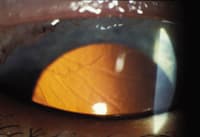

Examination: Examination revealed a peripheral retrocorneal membrane on the superior cornea. (See photographs, below.) Gonioscopy revealed epithelialization of the angle and formation of peripheral anterior synechiae (PAS). The diagnosis of epithelial downgrowth was confirmed with argon laser photocoagulation.

| Left: A slit lamp photo of the superior cornea demonstrates a scalloped, gray line representing the multicellular, thicker leading edge of the epithelial sheet. Right: Retroillumination of the superior cornea shows the thickened leading edge of the posterior corneal epithelial layer. | |